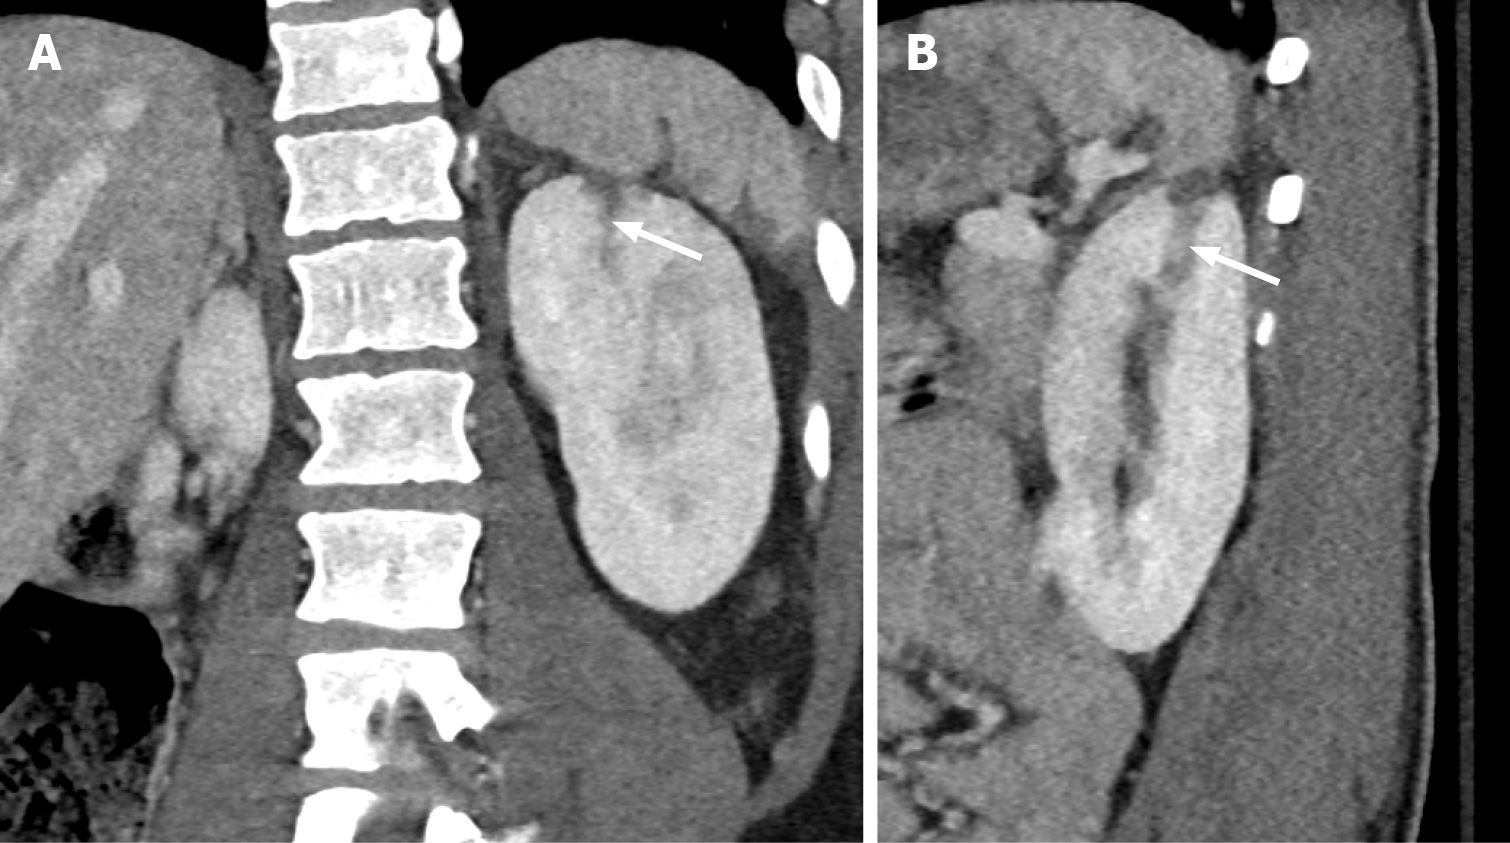

Figure 2 Grade III renal Injury.

A: Coronal view; B: Sagittal view. A linear area of hypoattenuation of 1 cm depth in the left superior renal pole (white arrow), consistent with renal laceration corresponding to grade 3 renal injury.

Figure 3 Grade III renal Injury.

A: Non-contrast computed tomography obtained during biopsy of the left kidney with the patient in the prone position, demonstrating the biopsy needle with the tip abutting the left inferior renal pole (white arrow); B: Follow-up arterial phase computed tomography abdomen 48 hours later demonstrates left subcapsular and retroperitoneal haemorrhage (black arrow) with an area of contrast blush in the inferior renal pole consistent with pseudoaneurysm (white arrow).